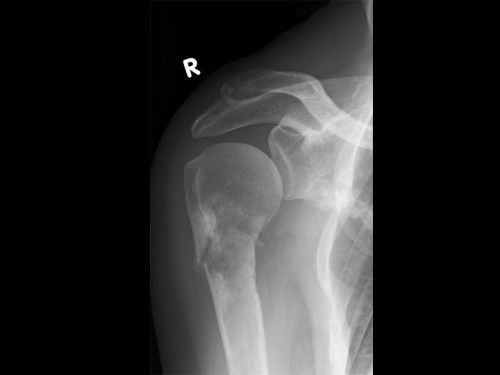

63-jährige Patientin. Bei ihr ist ein operiertes Mammakarzinom vor 3 Jahren bekannt. Das Ausgangsstumorstadium war: pT2, pN 0/1 (sn), L0, V0, cM0, R0, G2. Aktuell plagen sie Schmerzen in der rechten Schulter, die insbesondere bei Bewegung auftreten. Ein Trauma hat nicht stattgefunden.

Untersuchungsbefund der rechten oberen Extremität:

- Weichteilschwellung und Druckschmerz über Schulter und proximalem Oberarm

- Aktive Beweglichkeit des Schultergelenkes schmerzbedingt erheblich eingeschränkt